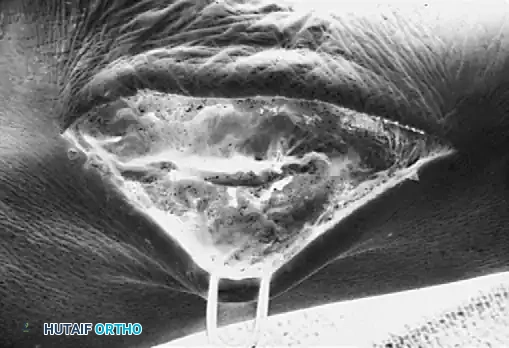

جراحة إزالة التحام العقب والزورقي

في حالة التحام العقب والزورقي، يعتبر الاستئصال الجراحي للجسر العظمي هو الخيار المفضل، خاصة لدى الأطفال والمراهقين الذين لا يعانون من خشونة في المفاصل.

يقوم الجراح بإزالة الجسر العظمي بالكامل لضمان عدم عودته. ولمنع تكوّن العظم مرة أخرى في نفس المكان، يتم وضع نسيج عازل في الفراغ الناتج، مثل جزء من عضلة مجاورة (Extensor digitorum brevis) أو نسيج دهني، أو استخدام الشمع الطبي. أثبتت الدراسات أن هذه الجراحة تنجح بنسبة عالية في تخفيف الألم واستعادة جزء كبير من حركة المفصل.